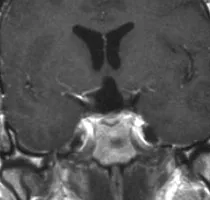

手术顺利,术后患者神经系统无新发异常表现。由于垂体功能不足,需要替代激素治疗。

术后复查MR:术后3年增强MRI显示肿瘤完全切除。